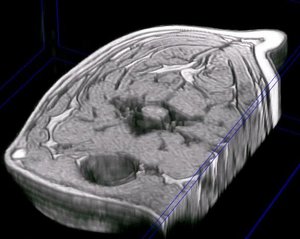

Detalle de la columna vertebral cervical de un perro. Resonancia magnética |

detalle de la columna vertebral cervical en una reconstrucción en 3D del cuello de un perro a partir de imágenes de resonancia magnética (secuencia GE) |